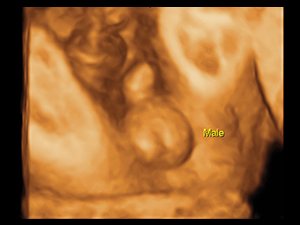

3D/4D Ultrasound

For a routine assessment of the fetal morphology, 2D ultrasound is already adequate. The addition of 3D and/ or 4D scan is a bonus and may enhance the bonding between the family and the unborn child. Most women also find it pleasurable watching the 3D/4D pictures of their babies. 3D/4D ultrasound is increasingly important when fetal abnormalities are suspected or picked up. These new modalities of ultrasound can help by clarifying the abnormalities. The 3D ultrasound pictures may also help the family appreciate to what extent the baby is affected.

3D fetal genital organ in a male fetus at 28 weeks